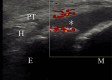

Methods: The study participants were junior baseball players who participated in a medical checkup in 2020. We included knees in the apophyseal stage evaluated using ultrasonography, and classified them into the bursitis and no-bursitis groups using color-enhanced Doppler ultrasonography. We also investigated bone lesions of the tibial tuberosity, determined by fragmentation of the bone and irregularity of the ossification center. Demographic data, practice duration, pressure pain on tuberosity, pain while playing baseball (visual analog scale), heel-buttock distance (HBD), straight-leg raise angle, and range of hip internal and external rotation were evaluated. Group comparisons were performed using the Mann-Whitney U test and Fisher exact test, and a logistic regression analysis was performed.